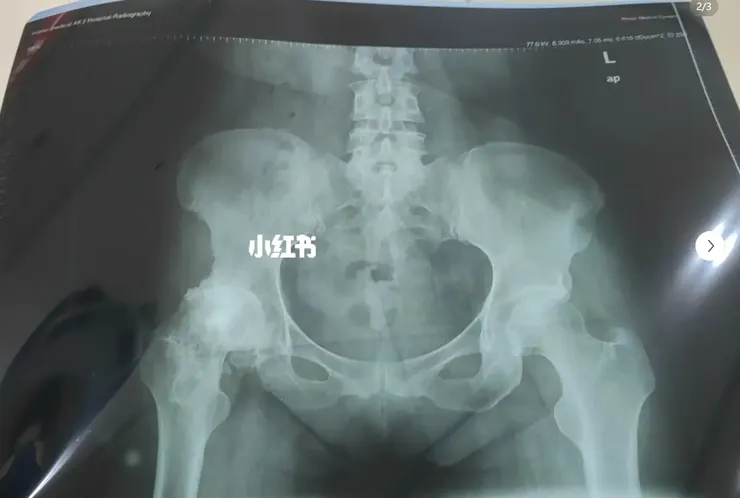

- 19歲時右腿股骨頸巨細胞瘤手術